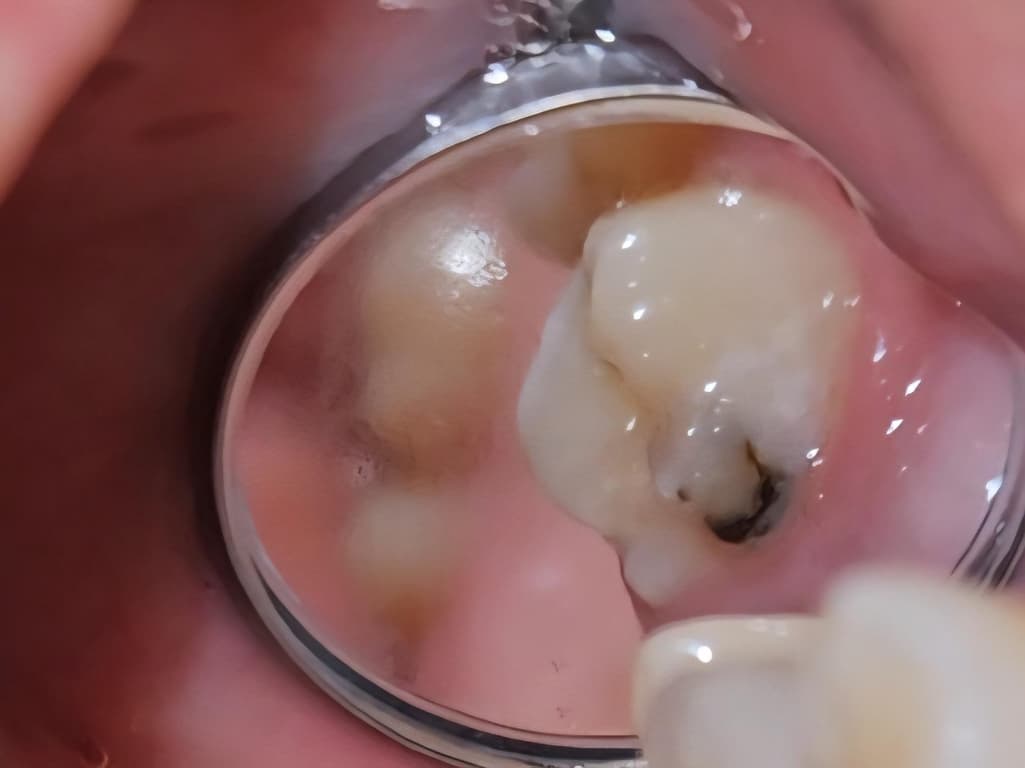

며칠전에 이를 닦고 사은품으로 받은 치아용 거울이 있길래 한번 쓱 봤는데 오른쪽 어금니 안쪽으로 이런 검은색의 무언가가 보이더라구요. 통증이 하나도 없어서 이런게 있는지도 몰랐고 2~3개월 전에 치과를 갔었는데 이쪽에 충치가 있다라는 말은 못들었어서 이게 충치가 맞나 싶어요.

그리고 이러면 안되지만 신경이 쓰여서 손톱으로 조금 긁어보니까 좀 긁혀서 나오는 것 같기도 한데 혹시 치석일 가능성도 있나요?

사진에 보이는건 충치가 맞습니다. 치과에 가셔서 엑스레이를 찍어보고 치료를 받아보시는게 좋을것같습니다.

사진으로 봤을 때의 경우에는 충치로 보입니다. 충치가 있다면 충치가 있는 부분을 제거하고 치과형 재료로 충전을 하거나 보철 치료가 필요할 수 있습니다

자세한 확인을 위해서 치과에서 진료를 받아보는 것을 권유드립니다.

충치가 아주 크게 있는 편으로 보입니다. 치과 가서 다시 검사 받아보시는 것이 좋겠습니다.

치석 아니고 충치일 확률이 높습니다 안쪽으로도 충치 진행된 것 같습니다 통증없는 충치도 물론 있습니다